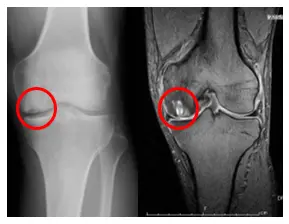

大腿骨内顆骨壊死

大腿骨の内側が血流不足になり壊死する病気です。

50歳以上に多く原因は不明ですが、ステロイドの大量使用、骨粗鬆症、外傷などが関連しているといわれています。